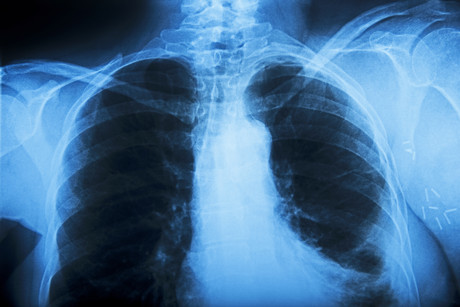

Are you genetically susceptible to lung disease?

A collaborative study involving the universities of Western Australia and Queensland has identified 43 new genes that may help those individuals most susceptible to deadly lung diseases such as asthma, emphysema, bronchitis, airway inflammation and airway narrowing.

Chronic obstructive pulmonary disease (COPD) is a reduction in lung function that can lead to symptoms that range from mild to severe. While it may not be a well-known acronym, it is the third-leading cause of death in humans.